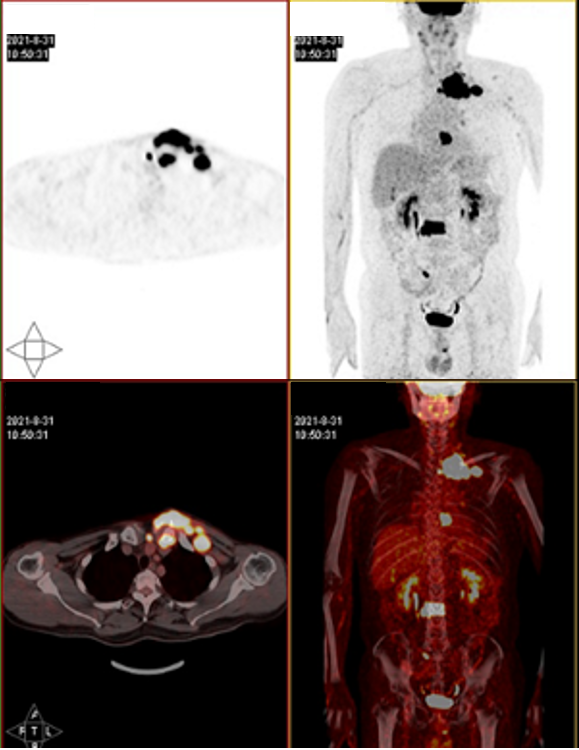

影像学检查

2021-8-31查PET-CT示:左侧锁骨胸骨端、胸8附件、腰3椎体骨质破坏伴软组织肿块、糖代谢异常增高,骶骨糖代谢异常增高灶,双颈、左锁骨多发肿大淋巴结,糖代谢异常增高,上述考虑恶性病变,血液系统肿瘤可能大,建议穿刺活检。

2021-8-31